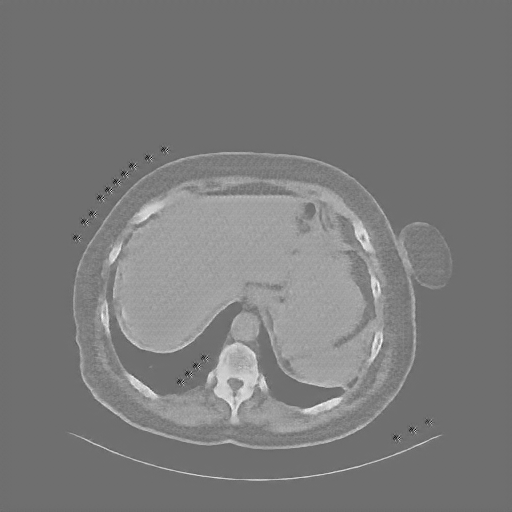

Reconstructed NATIVE CT scan (cycle consistency)

Full window (WL 1023.5, WW 4095 β†’ Low βˆ’1024, High +3071)

Actual HU range: [-620.4, 433.1]

Lung window (WL -600, WW 1500 β†’ Low βˆ’1350, High +150)

Actual HU range: [-620.4, 150.0]

Mediastinum window (WL 40, WW 400 β†’ Low βˆ’160, High +240)

Actual HU range: [-160.0, 240.0]